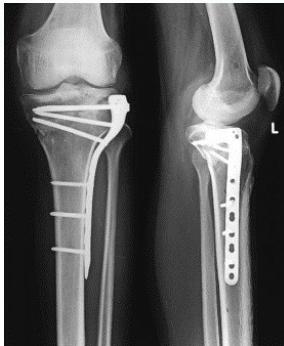

| Plate Types - Buttress Plate (T-Plate/L-Plate) | Indications: Lateral or medial tibial plateau fractures, distal radius fractures. | , , , ![]() |

| Plate Types - Anatomical Plates with Locked Screws | Indications: Metaphyseal fractures. Advantages: Anatomically contoured, excellent fixation in metaphyseal areas and osteoporotic bone. | , , ![]() |